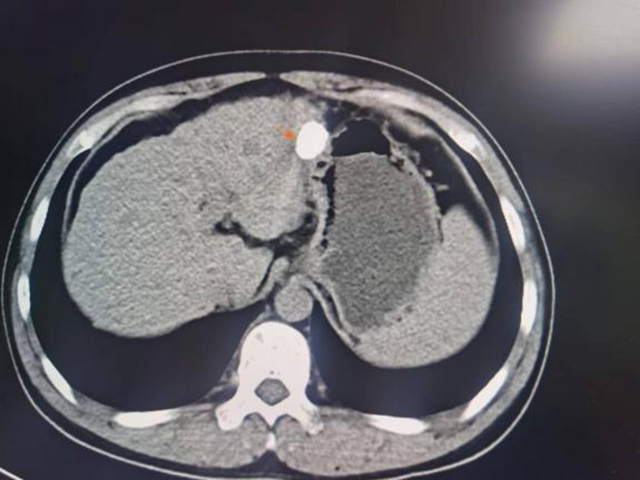

40多岁的解先生乙肝两对半异常有20余年了,2015年时在当地医院做CT检查提示:肝左外叶结节影,考虑为原发性肝癌。为寻求进一步诊治,解先生来到了西南医科大学附属中医医院就诊,肝胆病科医师接诊后为其完善了相关检查,确诊为原发性肝癌。

综合考量病情后,肝胆病科团队为解先生制定“肝动脉灌注化疗+超声引导下肝肿瘤消融”微创治疗方案。术前准备就绪后,肝胆病科团队顺利为其实施了手术,术后给予保肝降酶、抑酸护胃等处理,配合中医中药活血化瘀、疏肝解郁。而后定期随访复查,至今未发现肿瘤复发。

术前

术后